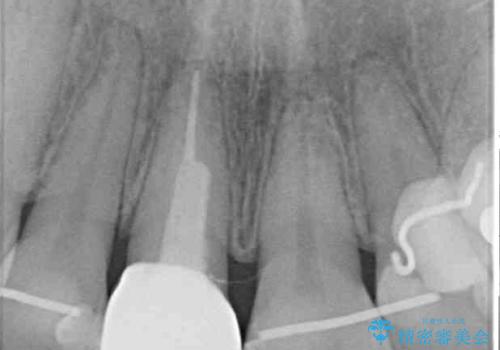

- 前歯の変色を気にして来院された患者様です。

ラミネートベニアによる治療を以前受けていたものの、神経組織が失活して以降、徐々に変色してきたとのことでした。

オールセラミッククラウンにて補綴治療を行うこととしました。

周りの歯と調和した、自然な仕上がりとなりました。